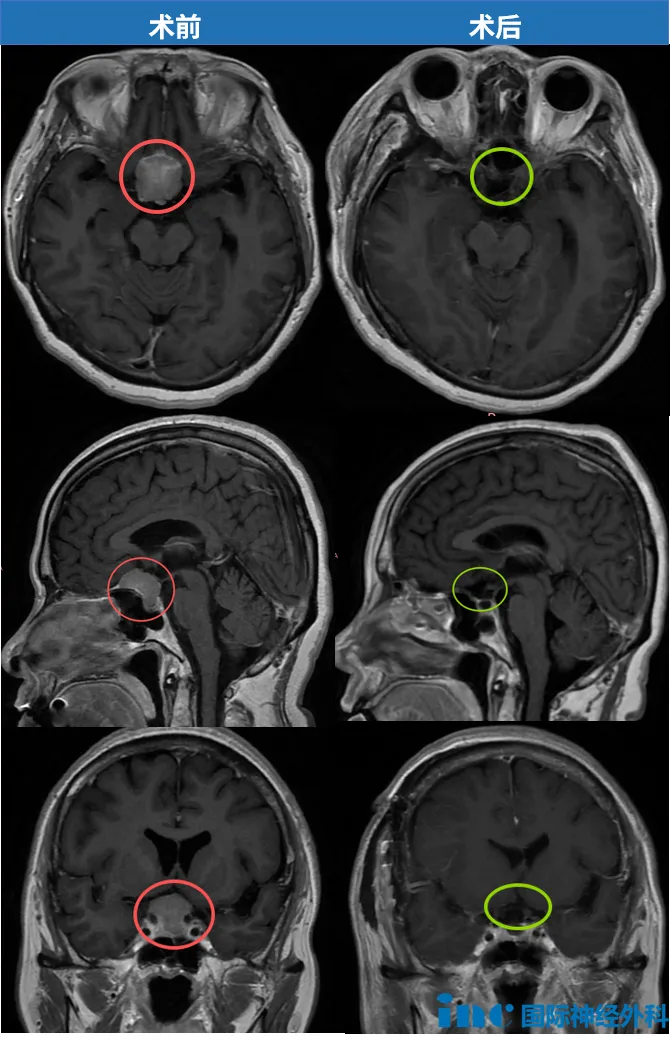

这是一场与时间的赛跑:58岁的陈女士罹患鞍区脑膜瘤,不仅位置险要,更已导致视力显著下降。危急关头,为了保住剩余的视力,一家人当机立断,迅速选择手术;巴教授更是精准出击,顺利切除肿瘤,从失明的边缘为她夺回了光明。

2024年12月17日,远在异国的陈女士因面瘫、视物模糊被确诊为鞍区脑膜瘤。病情不等人——短短4天后,她已紧急飞回国内。进一步检查显示,肿瘤匍匐于鞍底,约2.6cm×2.5cm。

由于这个肿瘤位于前颅底,从两条视神经之间生长,并随着其增大逐渐压迫了视神经。此外,肿瘤的位置十分险要,还波及到了垂体及垂体柄。

“一切顺利”!巴教授救下这“岌岌可危”的视力

术后当天,陈女士在ICU已能与教授自如交流,视力有所恢复,并于当日转入普通病房。这场与时间的赛跑,他们跑赢了。